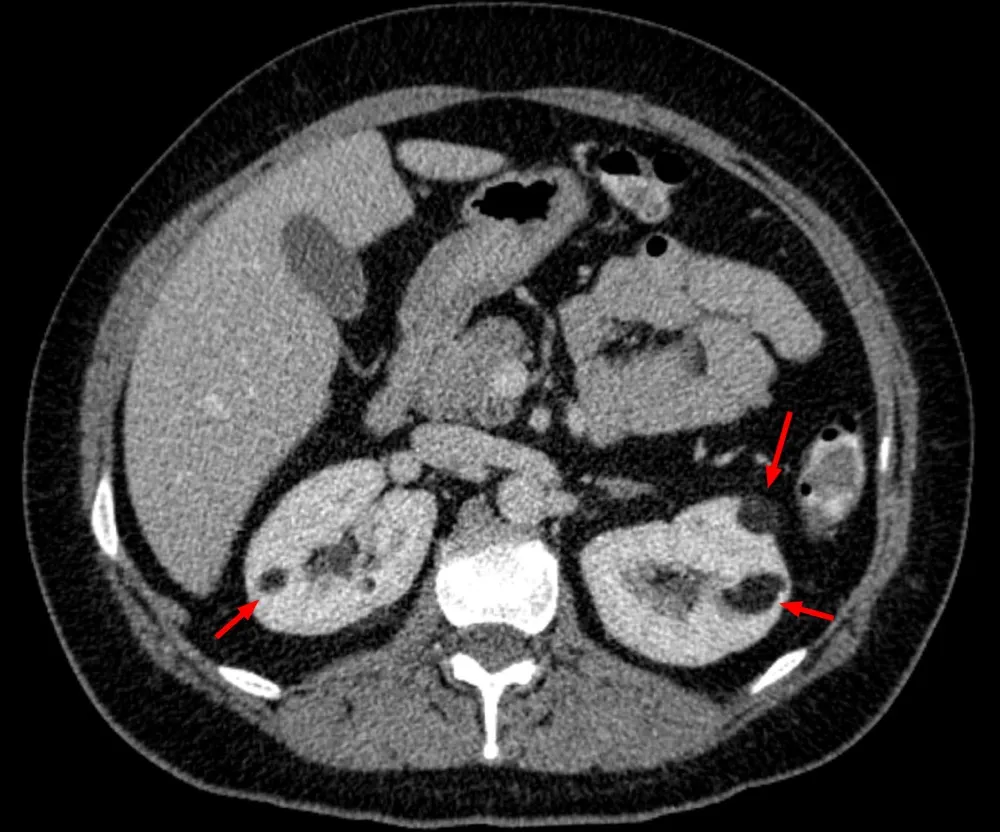

Particularidades da IRA e diálise no paciente cirrótico

Particularidades da IRA e diálise no paciente cirrótico